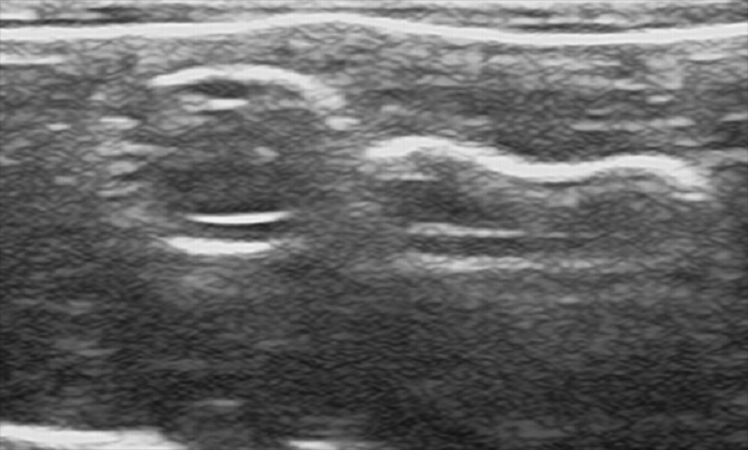

– Compatible with real ultrasound equipment for arterial and venous identification